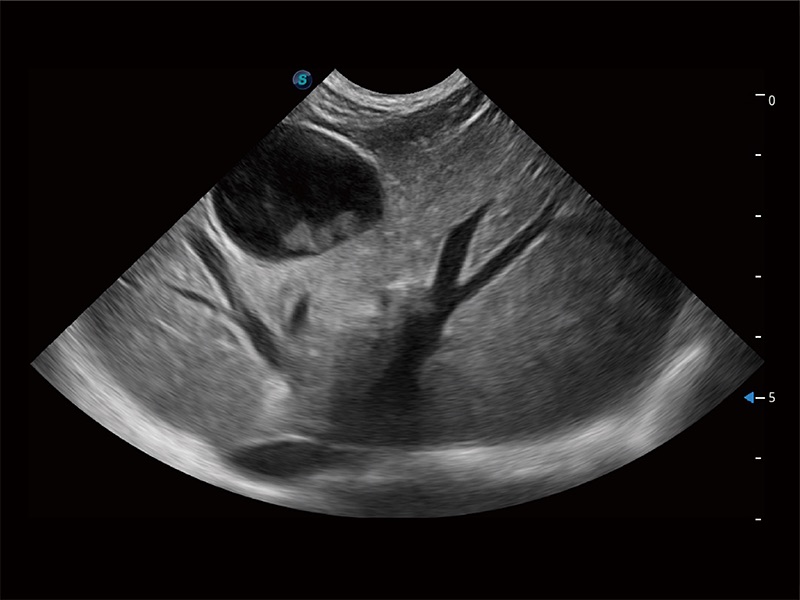

高性能和先进的临床应用工具可以为动物医生提供临床信心。ProPet 80 搭载了先进的腹部和浅表应用工具,帮助医生在日常临床实践中发挥前所未有的作用。

极大提升超低速微细血流的检出能力,同时更精准地滤除软组织和超声信号,为兽用医生提供以往无法通过常规血流获得的疾病诊断信息。

ProPet 80 专为动物医生设计,对不同的动物体型和生理结构作出了针对性的优化。通过动物影像专用软件,可满足个性化的应用需求,帮助动物医生获得更精确的诊断数据。

ProPet 80 全新的动物超声智能软件和丰富的探头群,为动物医生提供了高清晰度和精细分辨率的图像,无论在宠物、马科、畜牧还是实验室动物等应用中都可以轻松应对,为您的日常工作带来满意的体验。